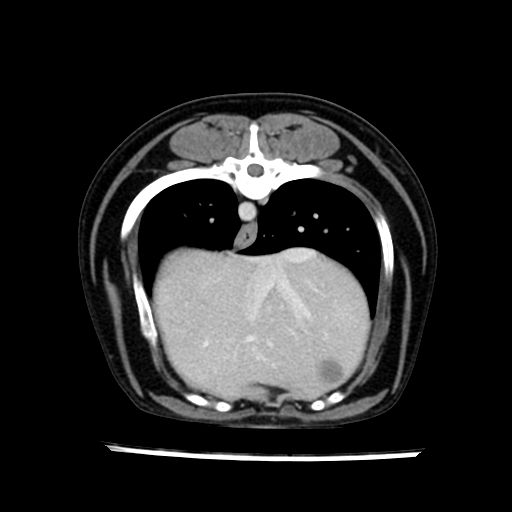

prescritto esame TAC

sequenza immagini limitata al fegato reni e surreni

le immagini ecografiche rispetto alla tac datano circa 7 mesi prima ,le surrenali sono normali nonostante il test acth sia risultato positivo .all’esame TAC dopo diversi mesi risultano aumentate armonicamente nel volume e si individua un forte sospetto di adenoma ipofisario .

sospetto adenoma ipofisario vs. meno probabilmente meningioma della base; intertiziopatia polmonare; lesione espansiva epatica, verosimilmente del lobo laterale sinistro, di sospetta natura neoplastica; lesioni spleniche di natura da definire; iperplasia/ipertrofia delle ghiandole surrenali, bilateralmente; vertebra di transizione del rachide toracico; tenosinovite cronica del muscolo bicipite brachiale di destra.